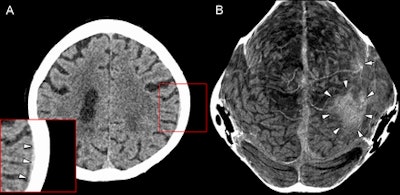

Figure A is a transverse section of a cranial CT image from a 58-year-old woman with a thin subdural hematoma (arrowheads) in the left parietal and temporal region. Lower left corner shows magnification. Figure B is a thin curved MIP of the skull vault. Arrowheads point to the large hematoma, while the single arrow in the left frontal region refers to a smaller hematoma. Image courtesy of Radiology.Retrospective evaluation